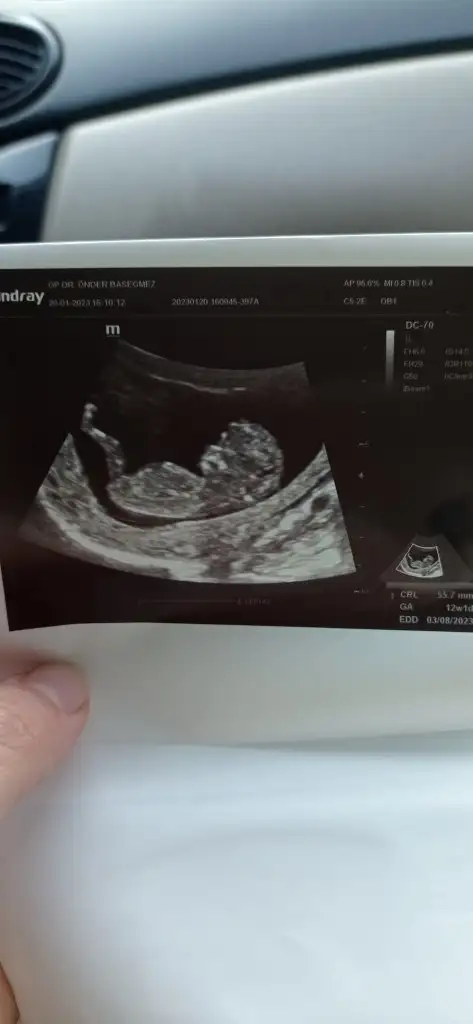

Bana bir daha yorum yapsana bebeğim yaaa 12+1 di bu hafta gttiğimde önde çıkmıştı günü 5 gün kdr. Normalde 11+3 tük Z Zzzzz00

Eklentiler

• 1675250561533.webp

15,6 KB · Görüntüleme: 72

• 1675250561567.webp

13,9 KB · Görüntüleme: 71

• 1675250561601.webp

15,2 KB · Görüntüleme: 65

• 1675250561637.webp

12 KB · Görüntüleme: 67